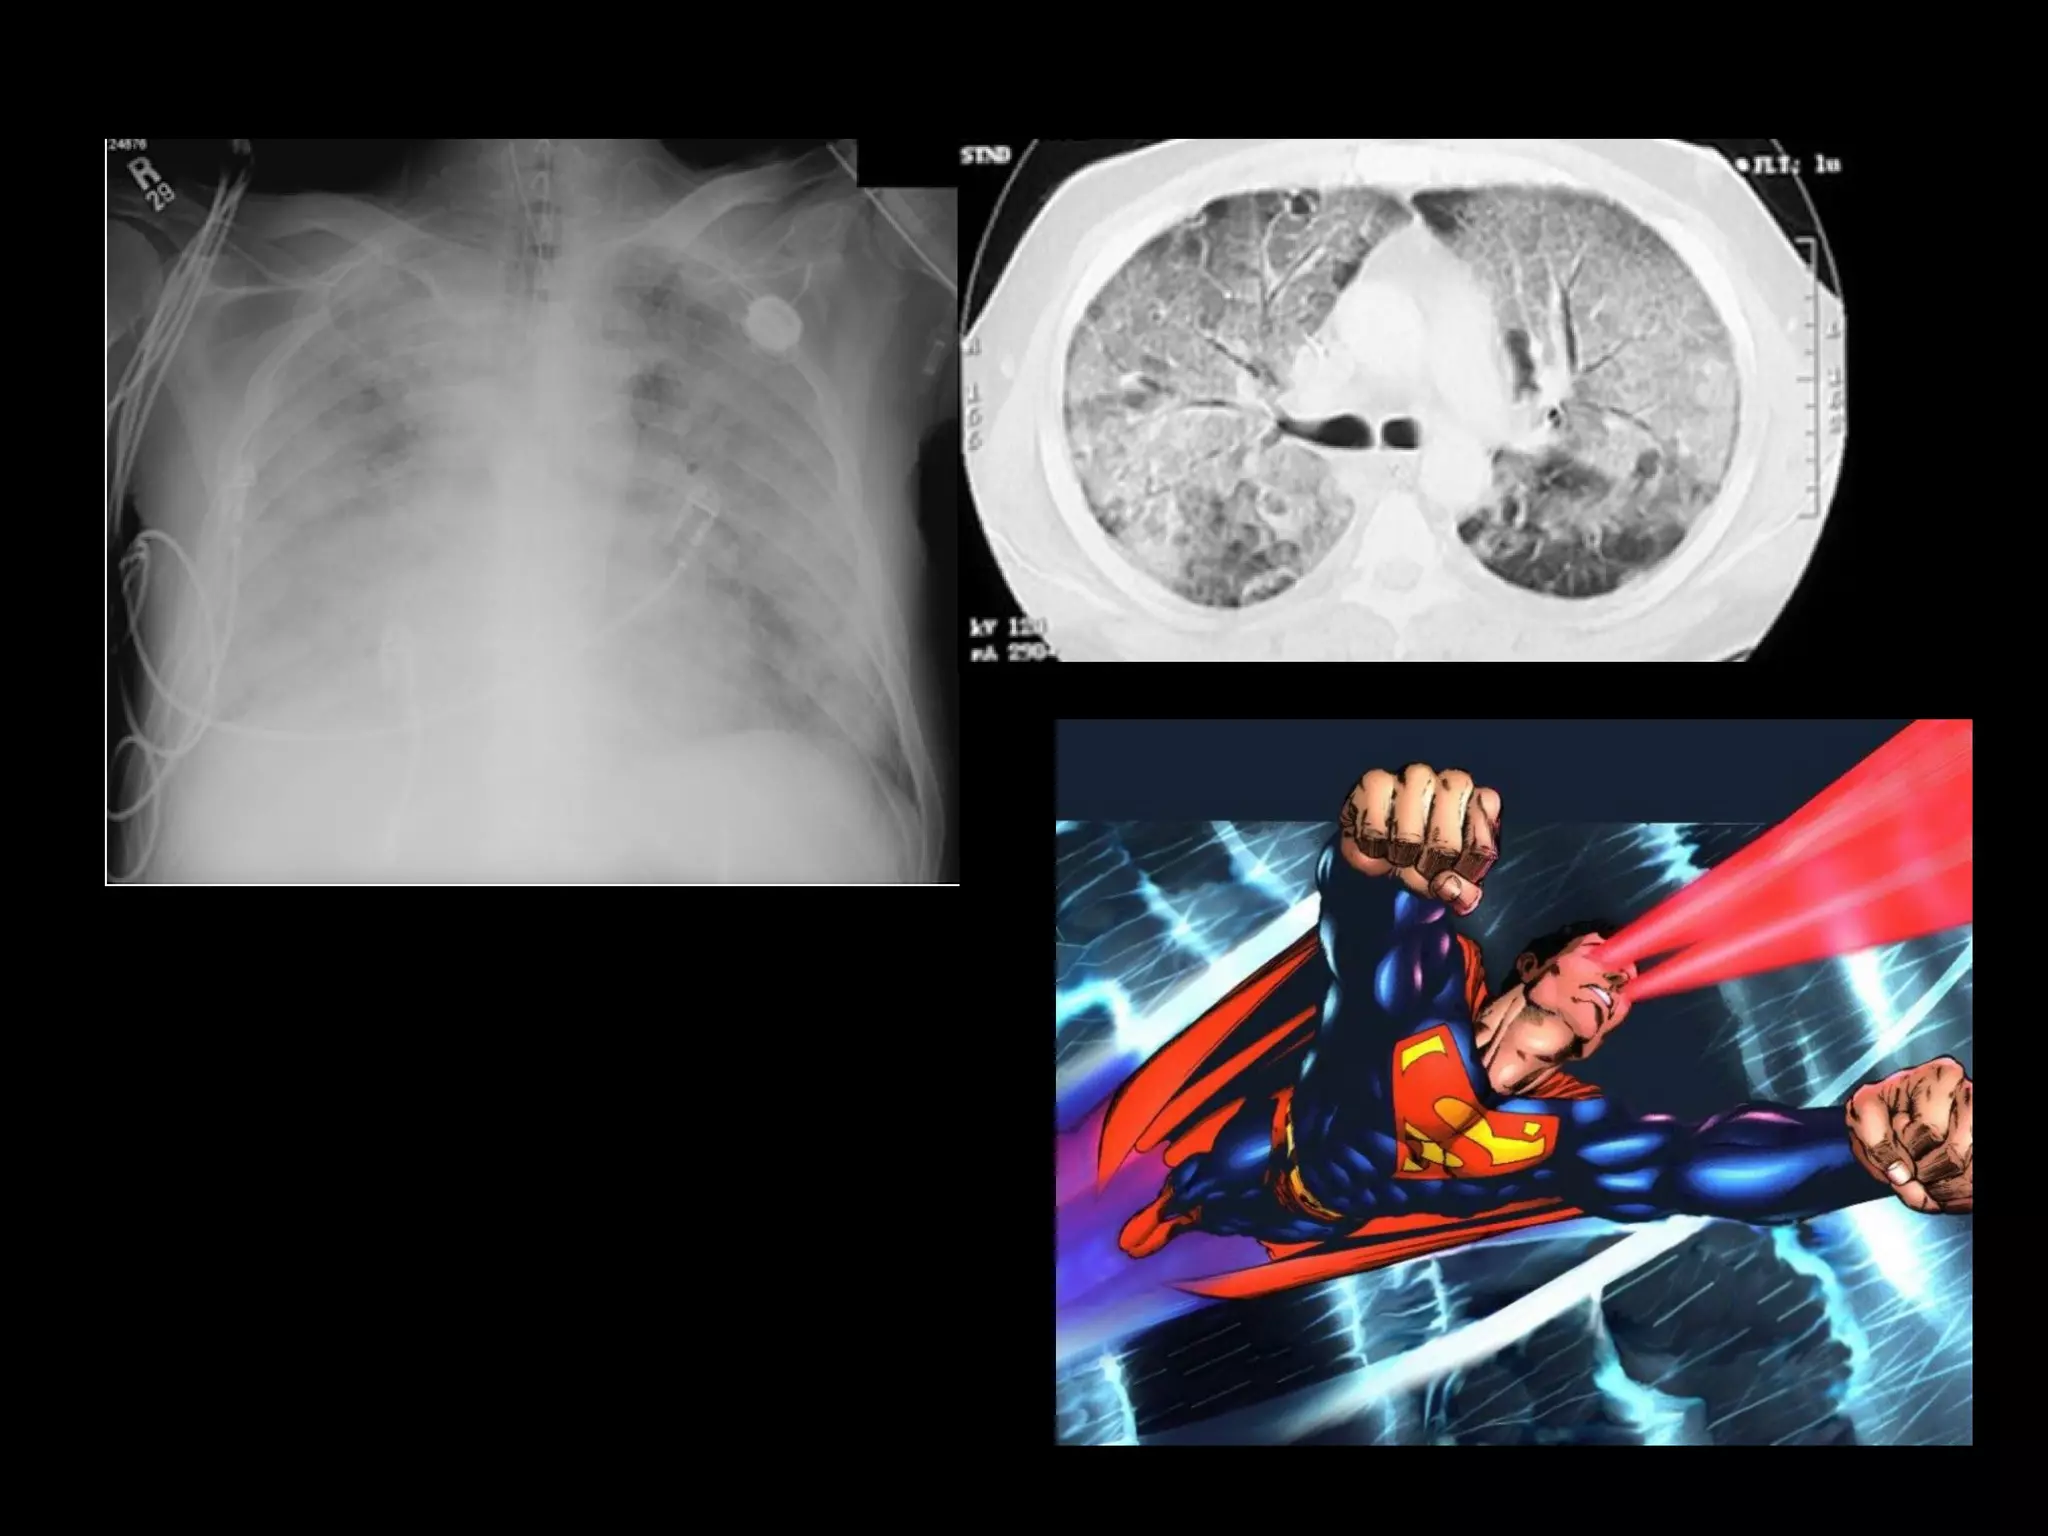

Retrieved in helicopter to

University Hospital

iNO treatment

Reduce vasopressors

Survivor